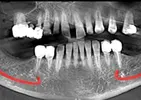

Implant treatment

Periimplantitis

Peri-Implant Mucositis